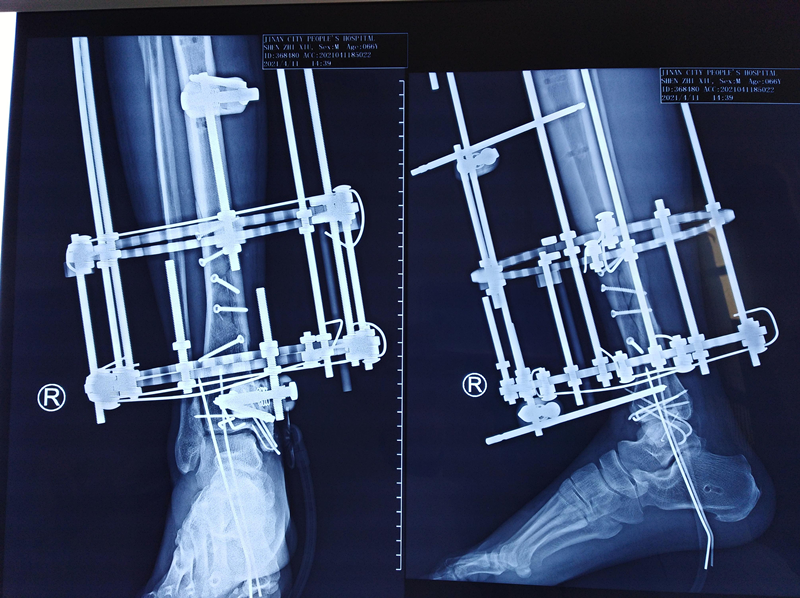

第三次手术图片

该患者车祸伤入院,入院查体可见右内踝皮肤缺损面积约5cm*10cm,右足背部皮肤脱套伤,内踝缺如。患者既往高血压、糖尿病,一直服用利血平及阿司匹林。利血平一般建议停用2周,阿司匹林建议停用1周方能进行麻醉。不手术,患者开放性损伤,持续流血状态,失血过多会发生生命危险。手术的话,服用利血平有术中发生血压不能维持,呼吸心跳骤停的风险。麻醉医师团队及创伤骨科医师团队面临双重风险,两害相权取其轻。患者开放性损伤,时间就是生命。面对困难,勇于承担,经患者及家属同意,第一时间进行了第一次清创+外固定支架固定+VSD负压引流手术。后续又进行了第二次清创+外固定支架调整+抗生素骨水泥链植入+克氏针固定踝关节骨折+VSD负压引流手术。第三次清创+骨折复位螺钉内固定+内踝重建+Ilizarov环形外固定固定+VSD负压引流手术。手术均进行顺利。

患者术后第一天进行膝关节、踝关节以及足趾关节、股四头肌收缩锻炼。术后第三天扶拐下地站立,现在已经可以适度负重锻炼。患者骨折无感染,无神经血管损伤,无内外翻畸形,肢体活动轻微受限制,步态正常且疼痛消失,临床疗效评价优。该手术的顺利实施,标志着创伤骨科在复杂创伤救治水平方面又更进一步。

据悉,胫腓骨骨折约占全身骨折总数的9.7%-13.7%。胫腓骨开放性骨折临床多见,多由高能量损伤所致,常合并多发性损伤,外固定支架是临床治疗的主要手段之一。目前,临床常用外固定支架类型主要有半环式、全环式、双边式、单边式以及组合式。Ilizarov环形外固定支架较其他单边外固定支架具有优良的力学性能。环形外固定支架最早由前苏联专家Ilizarov推广并应用。Ilizarov环形外固定支架治疗复杂开放性胫腓骨骨折具有固定牢固、安全可靠、可以进行骨延长及骨短缩治疗、创伤小、并发症少及可以早期下地负重并进行功能锻炼,但存在外架笨重,不方便生活护理的缺点。对于一些常规手术不能治疗的患者可以考虑作为一种选择。